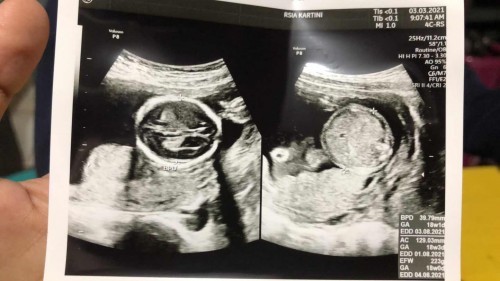

Awalnya gatau kalau lagi hamil, soalnya 4 kali testpack dalam sebulan hasilnya selalu negatif. Dan karena pengantin baru dan emang kurang tahu mengenai kehamilan, dibulan pertama pernikahan saya rajin melakukan testpack, tapi selama beberapa hari setelah testpack negatif ini saya sering muntah, mual, pusing. Jadinya suka binggung ini hamil atau gimana, testpack juga hasilnya negatif. Sebulanan setelah nikah saya mencoba lagi beli testpack dengan harapan pas hari datang bulan mau coba test, Alhamdulillah pas subuhnya saya testpack yang ke5 dan hasilnya Positif demi apa seneng banget sampai gemetaran ngasih tahu suami yang lagi tidurđ . Akhirnya memberanikah diri ke dokter kandungan untuk mengecek apakah benar hamil atau gimana dan Alhamdulillah beneran ada kantung kehamilan seperti foto USG yang saya upload MasyaAllahđ„ș. Gatau sugerti atau gimana, setelah tahu beneran hamil jadinya pengen makan daging mulu, lebih sering makan bakso dimanapun dan kapanpun wkwk. Terus banyak yang ngira aku hamil anak cowok soalnya katanya kalau suka makan daging anaknya cowok, ternyata Alhamdulillah USG diminggu ke 18 anaknya cewekđ„° semoga sehat sampai lahiran para calon ibu maupun ibu yang lagi mengandung Aamiin Allahumma Aamiinđ€Čđ» #CeritaNgidamTAP